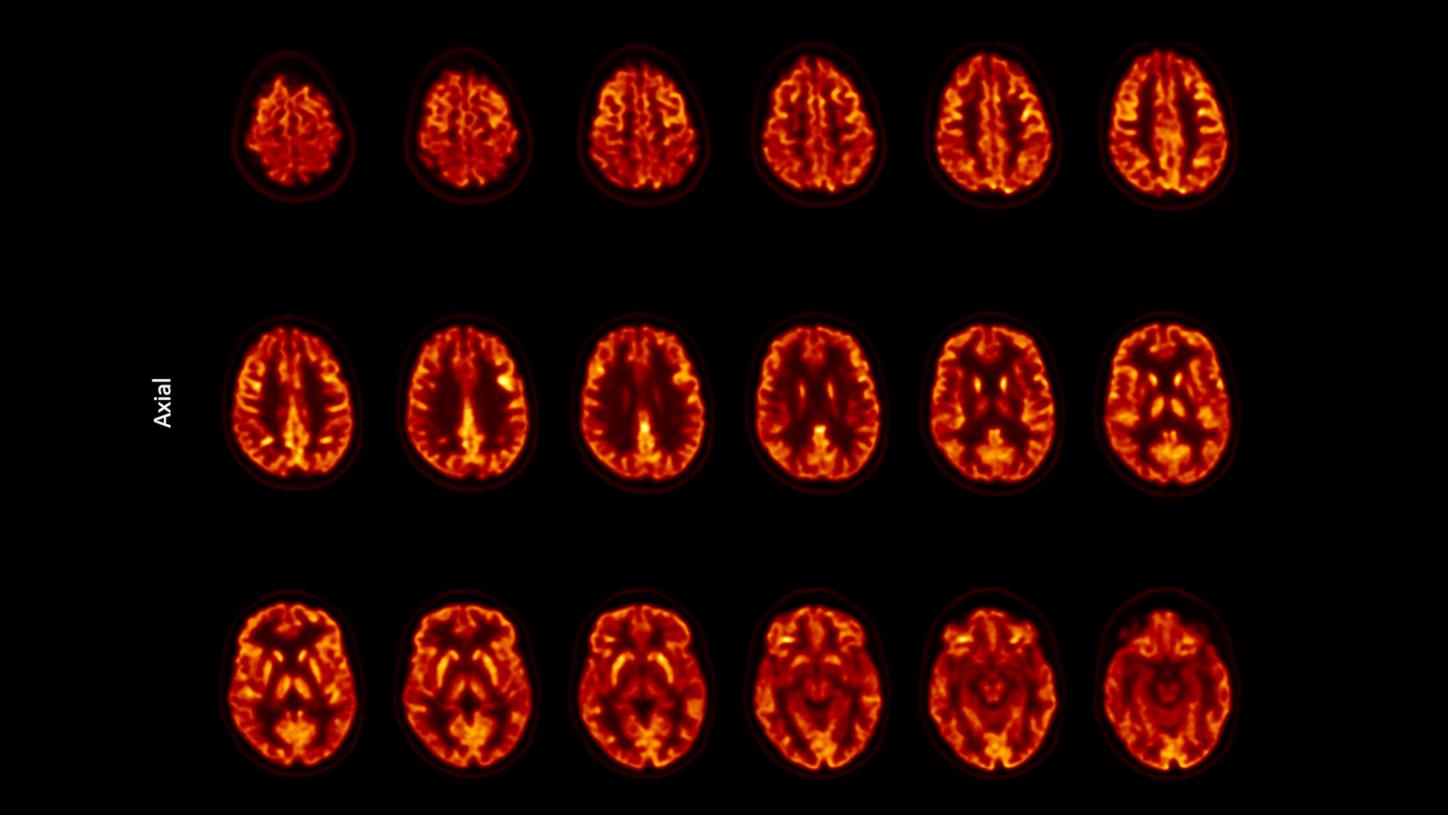

Biograph Trinion.X comes standard with proprietary X-Class detector technology, delivering 197-ps time of flight (TOF)2 for better lesion detectability. This impressive performance boost makes Biograph Trinion.X the only air-cooled PET/CT with < 199-ps TOF3 and an effective sensitivity up to 557 cps/kBq2,4—resulting in better lesion detectability and fast scans at lower doses.5

Gain accuracy, throughput, and small lesion detectability.